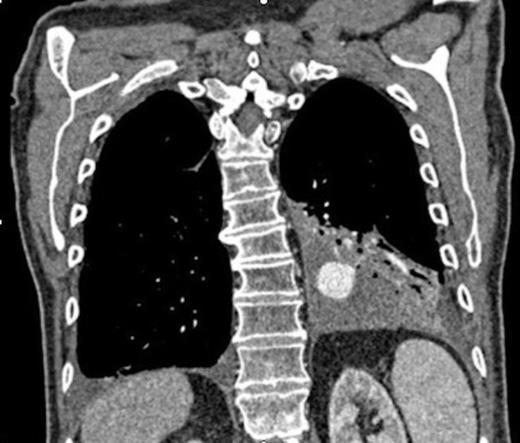

Coronal CT image in arterial phase demonstrating a 28mm diameter left lower lobe pulmonary artery aneurysm in association with a fluid collection

Three days later he presented with significant haemoptysis. A CT pulmonary angiogram (CTPA) demonstrated an increase in size of the PAA from 14mm to 28mm (Figure 1) diameter. A radiology opinion was sought and the patient transferred to the angio-suite for intervention.